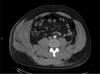

Which of the following conditions is a relative CONTRAINDICATION for use of the flap in the image shown for reconstruction of an 8 x 10-cm anterior ankle wound?

The correct response is Option D.

Diabetes mellitus can be associated with peripheral vascular disease, but by itself, would not prevent successful use of the reverse sural artery flap for foot or ankle reconstruction. Appropriate preoperative workup would include noninvasive ultrasound study of the lower extremity vasculature to prove the peroneal artery was patent.

The distally based sural artery flap receives its blood supply from a few sources, the most robust of which are perforators from the peroneal artery. The most distal of these perforators arise between 4 and 7 cm proximal to the lateral malleolus. Additional perfusion arises from neurocutaneous perforators from the sural nerve and venocutaneous perforators from the lesser saphenous vein.